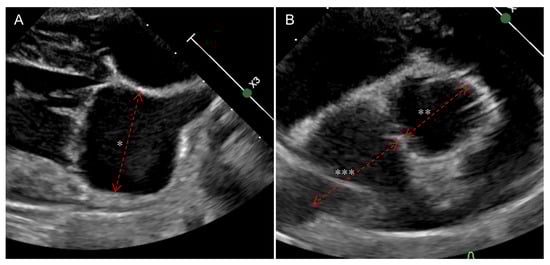

2.3. Echocardiography